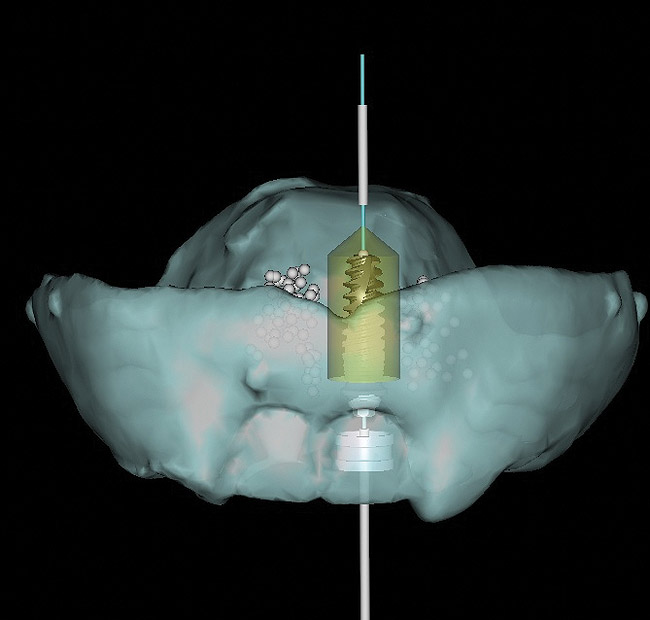

Figure 5  Surgical guide, “all-on-six” maxillary patient. Note right and left posterior guide sleeves for placement of 30-degree angled implants.

Figure 5

Panoramic and periapical radiographs are 2-dimensional (2-D) representations of a patient’s 3-D anatomy. Differences in radiographic machines and techniques can lead to image distortion, such as elongation and shortening of anatomy. Accurate evaluation and measurement of the relationship between the mental nerve, inferior alveolar nerve (Figure 4), or nasopalatine/incisive nerve, and the planned implant position can best be determined and planned by a 3-D evaluation of the anatomy as related to the planned restoration.3,30 Implant placement in patients in whom there is a question of nerve or sinus proximity is most accurate using “virtual” treatment planning and placement using CT-generated guides, thus minimizing potential patient morbidity. Technologies such as “all-on-four,” which is designed to maximize the intra-arch spread of implant platforms while avoiding the mandibular nerve and maxillary sinus, are excellent indications for CT-guided implant surgery (Figure 5 and Figure 6).